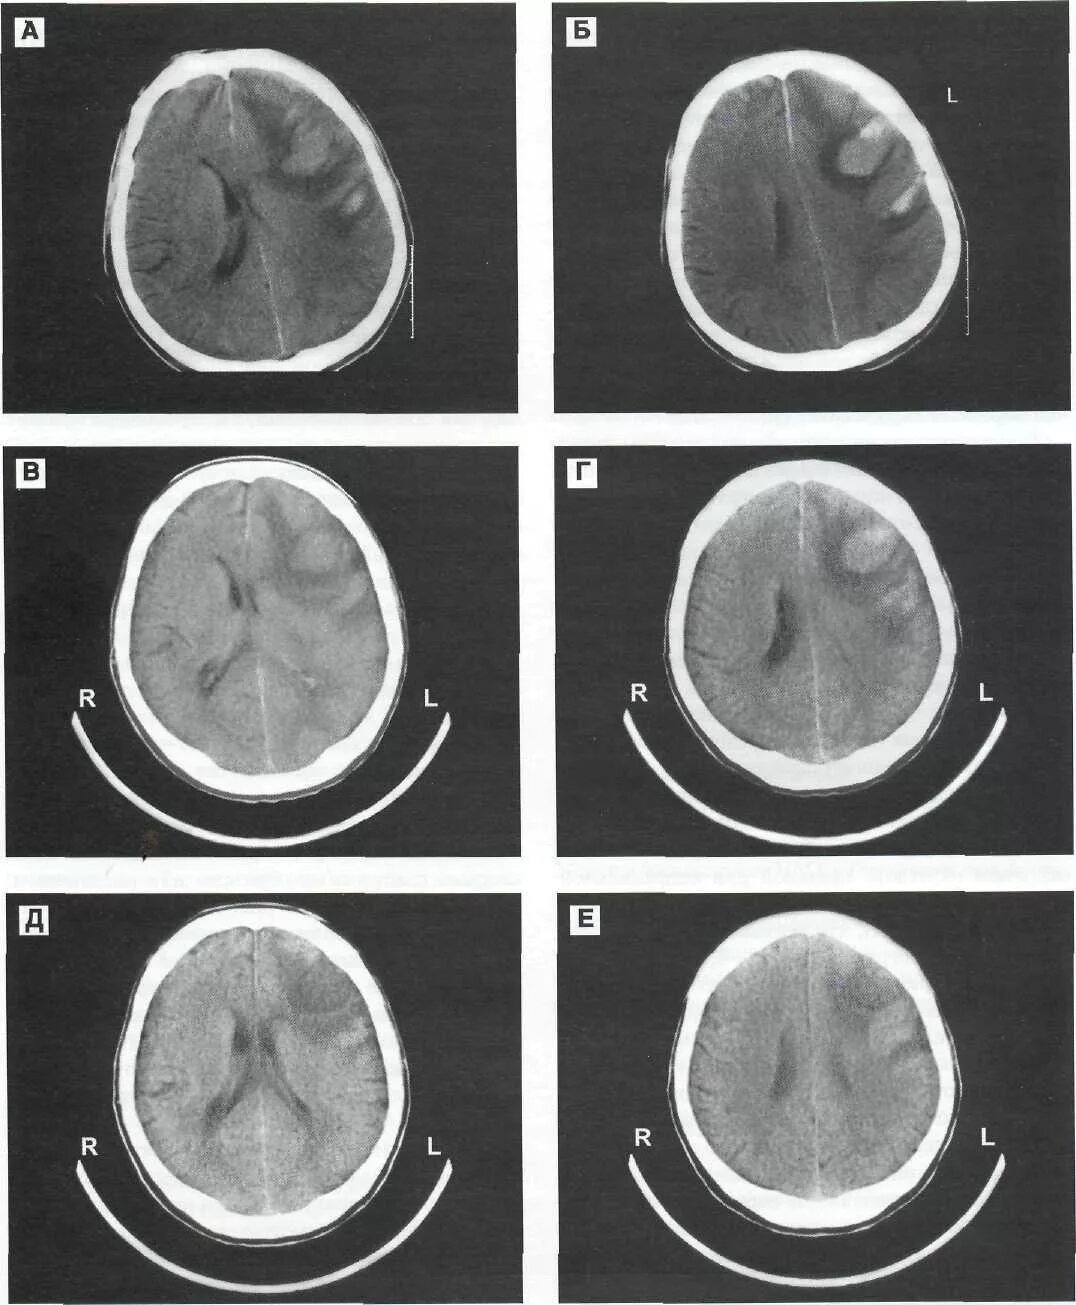

Гематома лобной